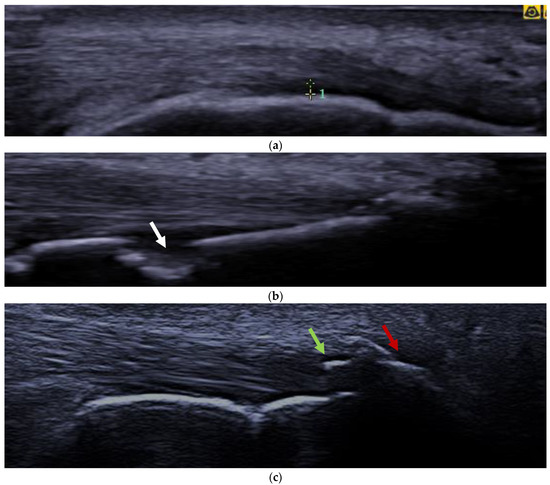

2.3. Ultrasound Assessment of EF